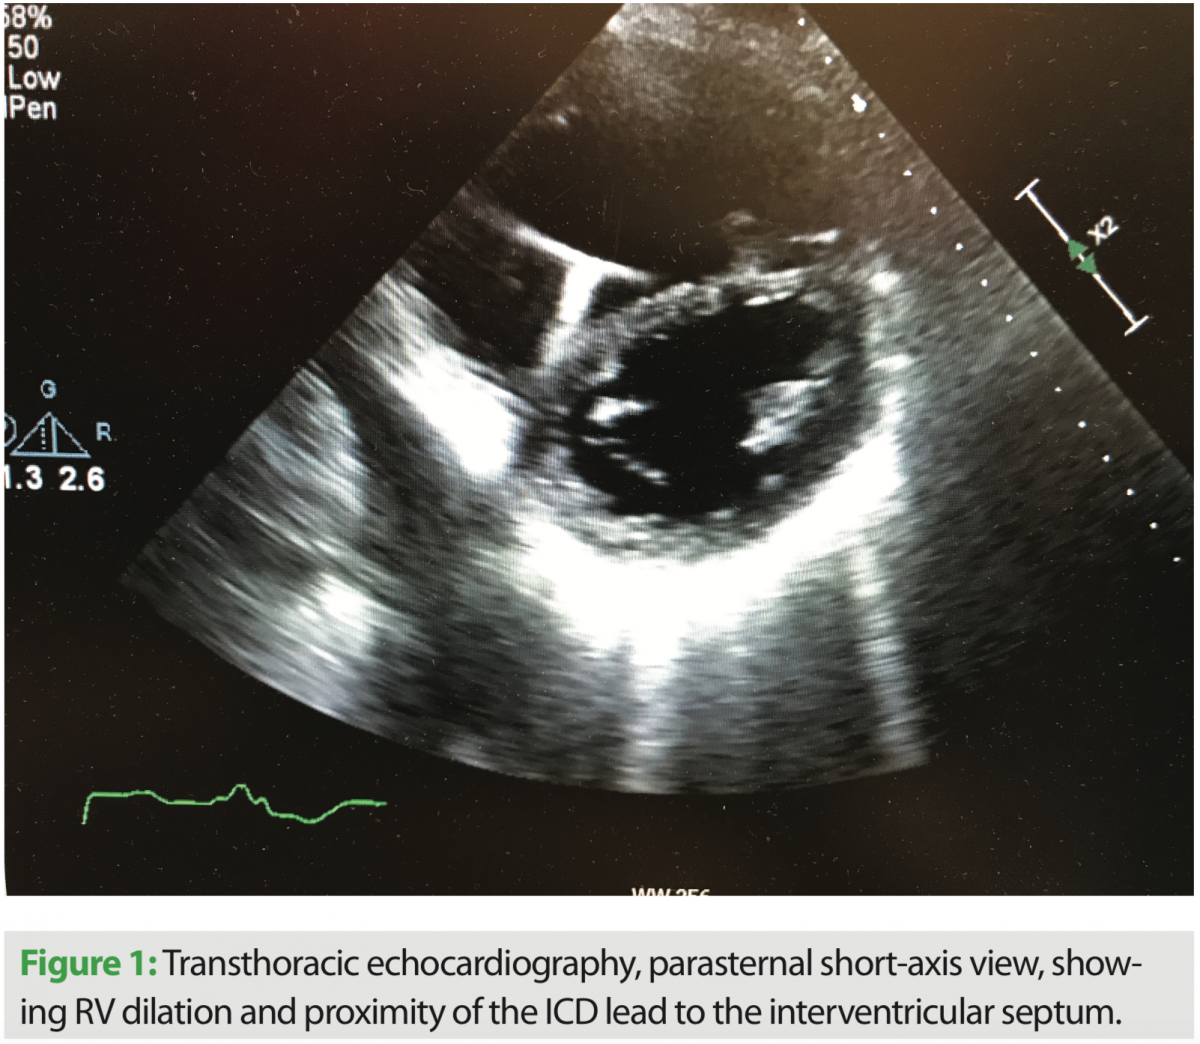

After admission and diuresis, significant symptomatic improvement occurred, and the patient was nearing his perceived dry weight based on initial clinic visits and recorded weights from home. Standard two- and three-dimensional transthoracic echocardiography were performed, and significant tricuspid valve regurgitation was seen. The course of the right ventricular lead can be seen in several views, along with its interaction with the TV leaflet and interventricular septum (Figures 1, 2, and 4). Corresponding tricuspid valve dysfunction is appreciated with severe tricuspid valve regurgitation on Doppler echo images (Figures 3 and 5). The RV was felt to be moderately dilated with a mid-RV diameter of 3.5 cm. Significant RV systolic dysfunction was seen and felt to be moderate with a tricuspid annular plane systolic excursion (TAPSE) of 1.25 cm. The tricuspid valve regurgitation was severe with a vena contracta width of 0.9 cm and PISA radius of 1.0 cm. LV systolic function was essentially unchanged, with an EF of 25%. The bioprosthetic aortic valve was well seen and without significant dysfunction.